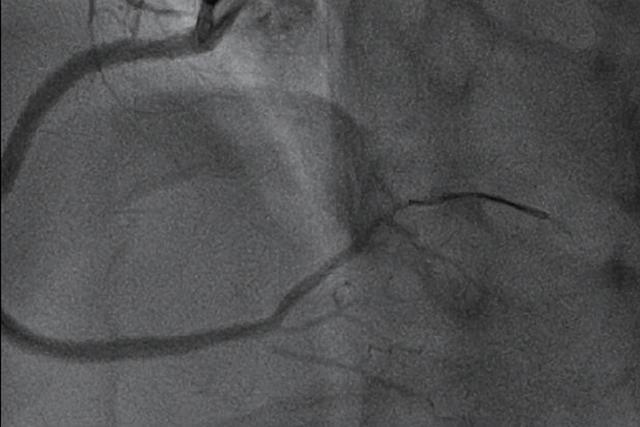

经ELCA处理后,IVUS可清晰显示右冠支架内机化血栓明显减少(图4)。此后,曹宇教授对患者右冠采用药物支架及药物球囊联合处理后,右冠血流恢复正常且无残余狭窄(图3)。

▲图3:治疗后右冠血流恢复正常